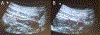

Ultrasound images comparing tissue planes for transversus abdominis plane (TAP) and quadratus lumborum (QL) blocks in non-pregnant patient (A) and immediately postcesarean delivery (B). Note the tissue distortion (flattened-appearing muscular planes) and air artifacts (arrows) that occur after cesarean delivery, which may introduce visualization and technique challenges for abdominal wall nerve blockade in this patient population. *Target for TAP block. **Target for QL block (QL1). ***Target for QL block (QL2). EOM, external oblique muscle; IOM, internal oblique muscle; QL, quadratus lumborum muscle; TA, transversus abdominis muscle.